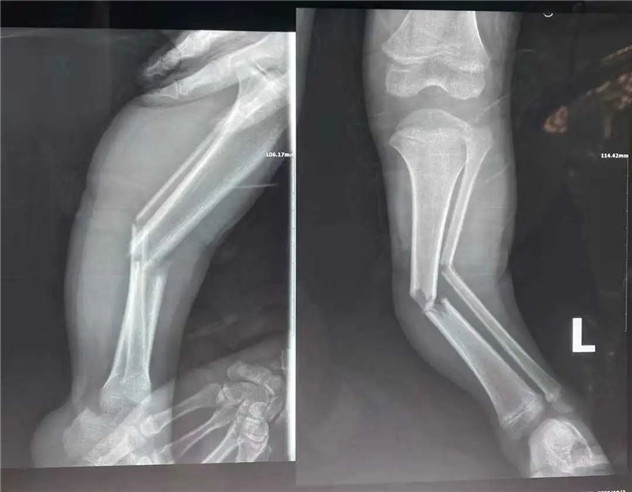

經(jīng)拍片顯示,睿睿左脛腓骨中段粉碎性骨折。接診的我院骨科中心主任羅軍建議其入院接受手術(shù)治療。

術(shù)前

據(jù)羅主任介紹,兒童骨折絕不是成人骨折的縮小版。兒童的不穩(wěn)定性脛骨骨折或雙側(cè)脛骨骨折,保守治療很難達(dá)到理想復(fù)位,可能會(huì)造成肢體不等長(zhǎng)、成角旋轉(zhuǎn)畸形、肌肉萎縮等并發(fā)癥。而彈性髓內(nèi)釘?shù)膽?yīng)用,正好解決了患者和醫(yī)生所擔(dān)心的問題,既理想地固定了骨折,又不影響肢體美觀,可謂一舉兩得。“彈性髓內(nèi)釘”技術(shù)可在保護(hù)骺板不受損傷的前提下,利用多點(diǎn)固定的原理,微創(chuàng)、有效地治療3—15歲的四肢長(zhǎng)骨骨折患兒。手術(shù)在C型臂全程引導(dǎo)下,只需在骨折遠(yuǎn)、近端各切一2—3cm切口打入彈性髓內(nèi)釘,創(chuàng)傷極小,不影響孩子的骨骼發(fā)育,對(duì)于骨折的愈合以及孩子以后骨骼發(fā)育影響小。相比之下,既有效避免了切開復(fù)位鋼板內(nèi)固定創(chuàng)傷大、疤痕大等缺點(diǎn),又有效避免了支架外固定鋼針外露、不易護(hù)理等弊端。